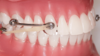

- A l'arcade supérieure : une ou deux petites tiges collées sur les canines (ou prémolaires) et allant jusqu’aux molaires.

- A l'arcade inférieure : une gouttière transparente et deux petites attaches collées sur les molaires inférieures

OU un arc lingual